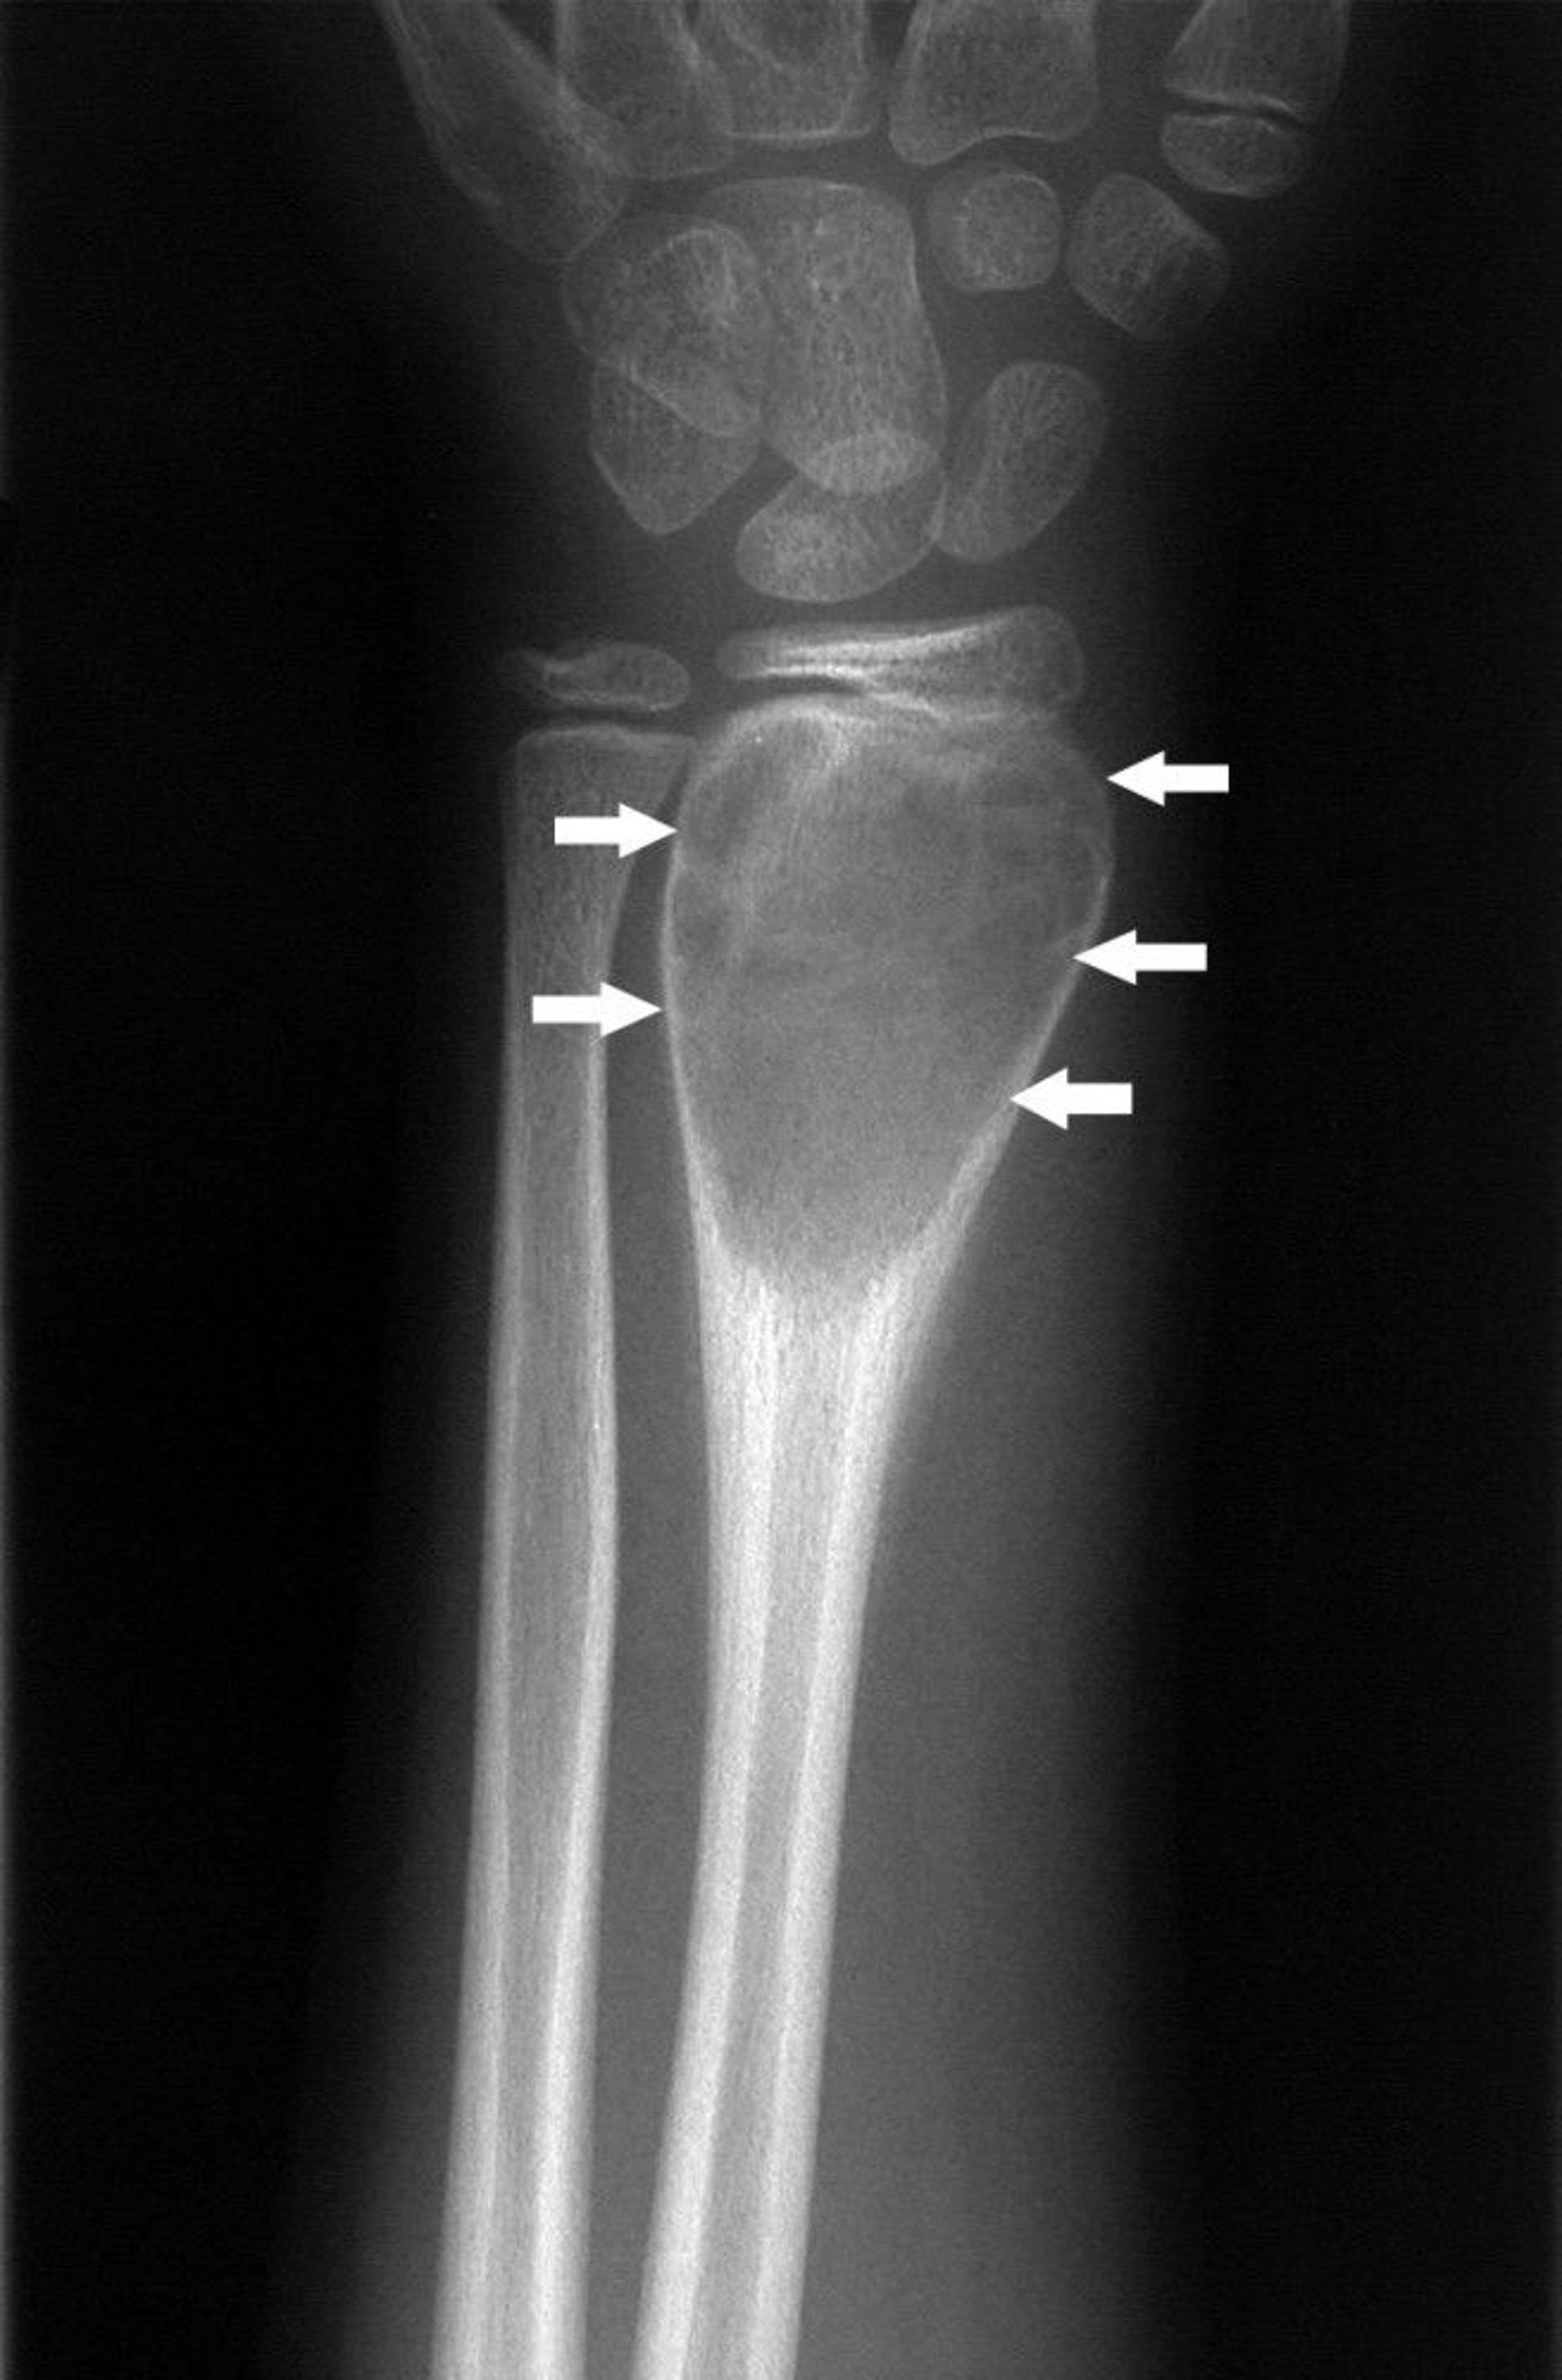

Aneurysmal Bone Cyst of the Wrist

This wrist radiograph shows periosteal new bone formation around the expansile lesion (arrows), which is characteristic of an aneurysmal bone cyst.

Image courtesy of Michael J. Joyce, MD, and Hakan Ilaslan, MD.